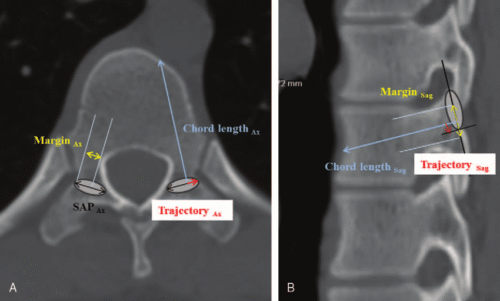

يقوم الأطباء عادةً بقياس زاوية الانحناء التقليدية لتحديد شدة اعوجاج العمود الفقري، ولكن الأشعة المقطعية تسمح أيضًا بقياس:

النقاط البارزة في منتصف الفقرة الخلفية (Spinous Process)

النقاط الجانبية للفقرات (Transverse Process)

مركز لوح الفقرة (Centre of Lamina)

هذه القياسات تساعد الطبيب على معرفة مدى انحناء العمود الفقري بدقة أكبر، وتوضح إذا كان الانحناء أكثر خطورة أو سريع التطور مقارنة بالطرق التقليدية.

استخدم الباحثون الأشعة المقطعية لقياس الزوايا المختلفة لكل فقرة: النقاط الخلفية، الجانبية، ومركز لوح الفقرة.